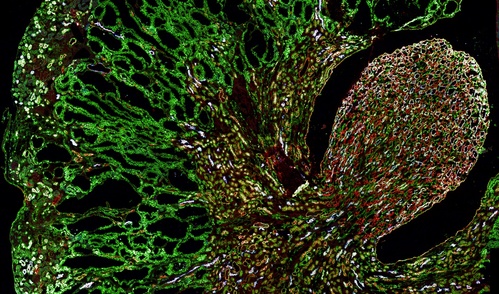

Misfolded MUC1-fs protein (green) builds up in the kidneys of a mouse model of MUC1 kidney disease.

Another area of intense focus is MUC1 kidney disease (MKD), a rare genetic condition with no cure. We have developed detailed mechanistic in vitro and in vivo studies aimed at understanding how mutant MUC1 causes the disease. We have also launched a full scale effort to identify therapeutic leads for the treatment of MKD.